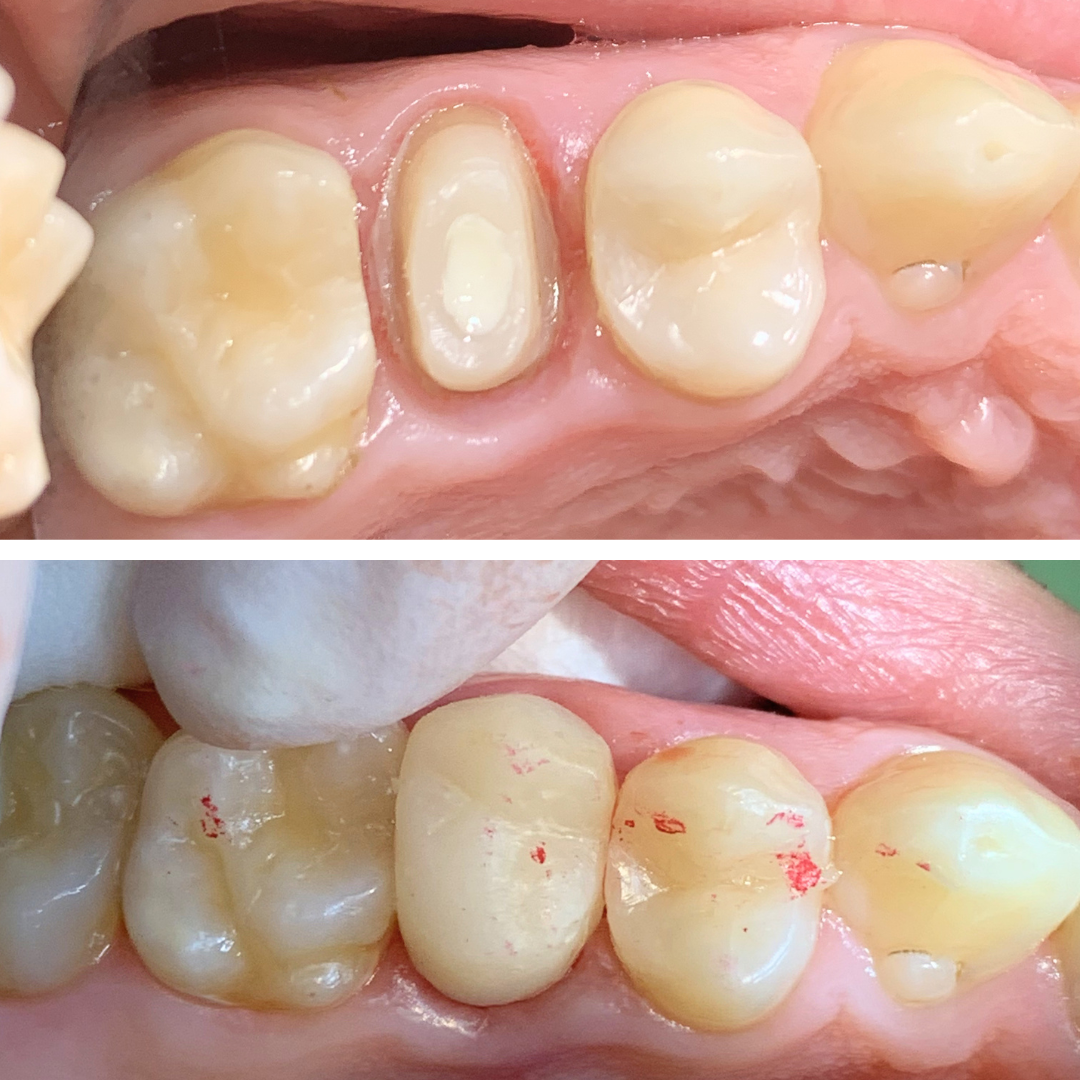

Aspectul restului radicular inainte si dupa indepartarea cariei.

Aspectul dupa reconstructia dintelui in vederea realizarii tratamentului de canal si realizarea unei coroane provizorii in cabinet.

Aspectul bontului dentar dupa aplicarea pivotului din fibra de sticla si gata de amprentat pentru a primi coroana definitiva.